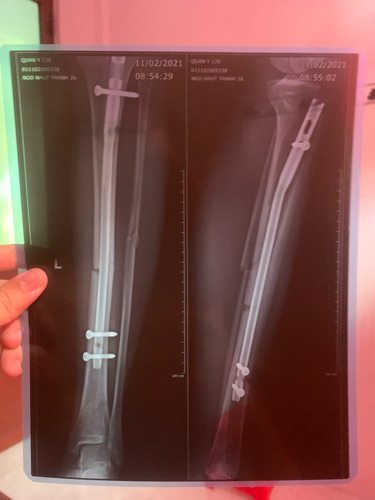

Chào bác sĩ, e phẩu thuật được 1 tháng 20 ngày, 2 phim này cách nhau 1 tháng, bá sĩ cho e hỏi với kết quả này có bình phục tốt không bác sĩ...e cần làm gì để bình phục tốt ạ...e cám ơn bác sĩ!

Chào e, phim e gửi sau điều trị đã bắt đầu hình thành can xương Cần 4-6 tháng để liền cứng E nên ăn uống tăng cường Calci và vitamin D kèm theo tập luyện vận động trị liệu PHCN để đạt KQ tốt nhất nhé